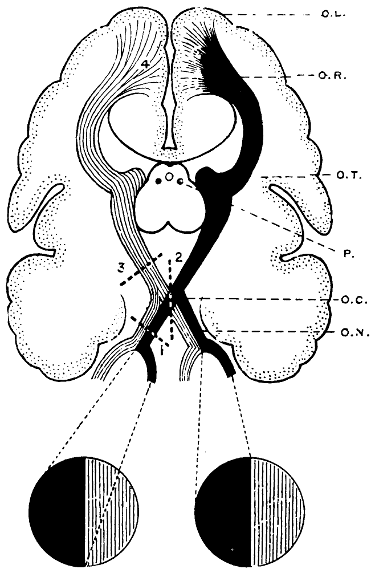

| 69. The visual paths | 223 |